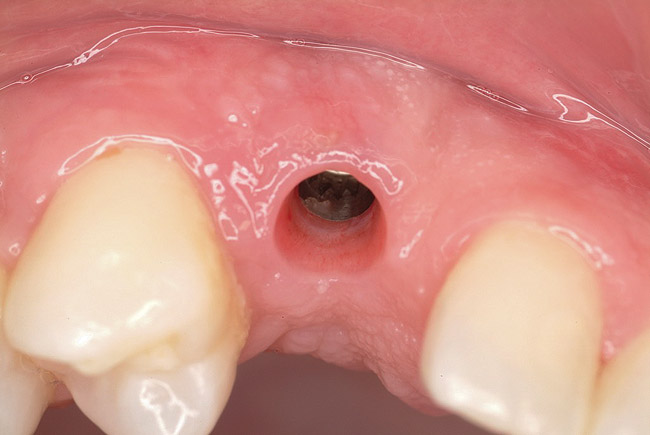

Figure 10   Soft-tissue contouring 10 weeks after implant insertion.

Figure 10

Ten weeks after implant insertion, the patient presented to begin soft-tissue contouring via a fixed, provisional crown (Figure 10). Deliberate under-contouring of the cervical portion of the temporary restoration was performed to avoid unwanted mucosal recession and possible esthetic complications (Figure 11 and Figure 12).